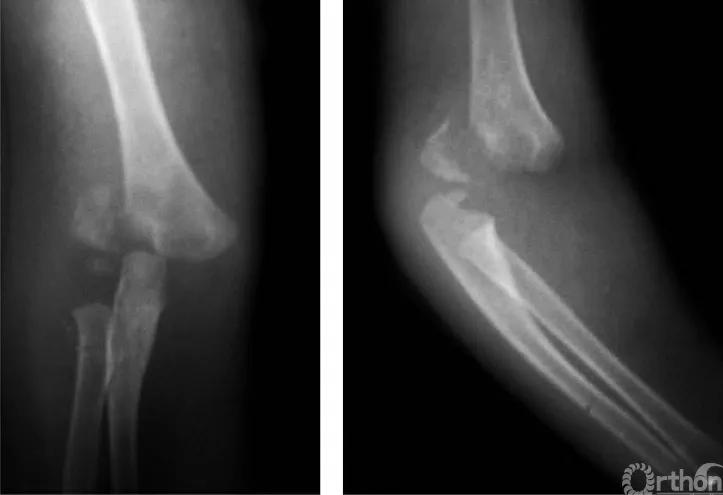

四、屈曲型

例:肱骨下端骨骺分离伴前臂向前移位(图4)。

图4